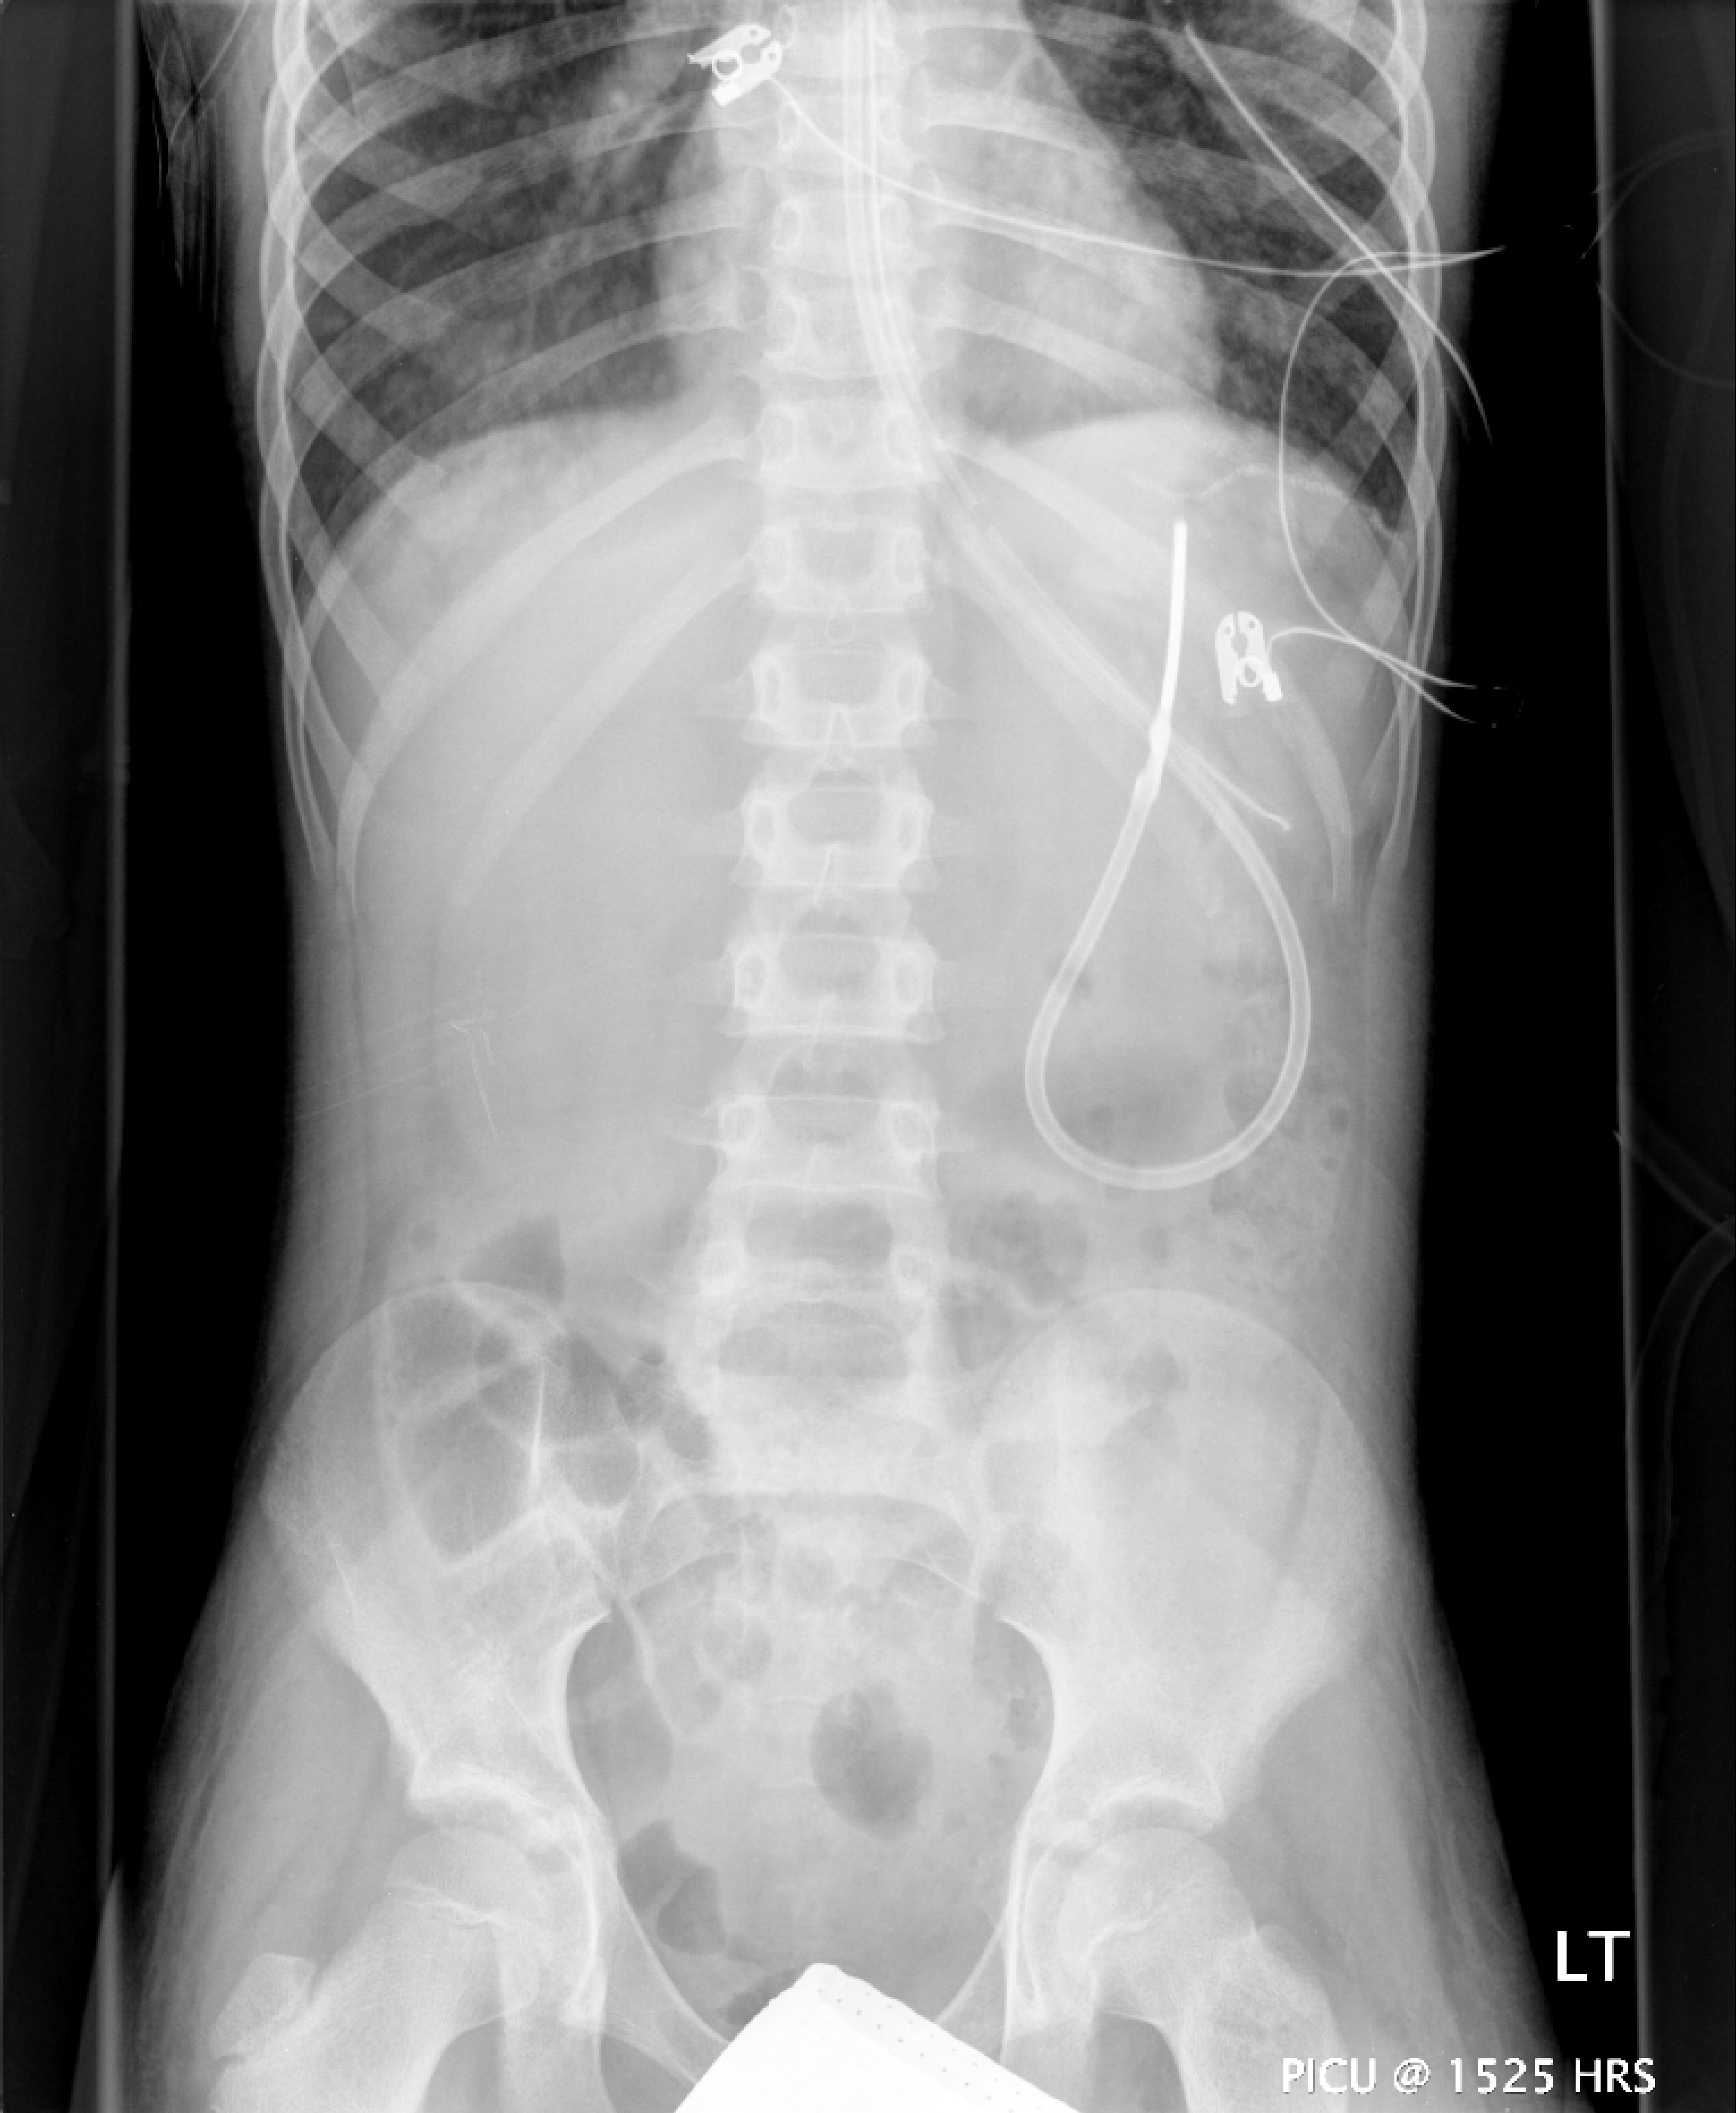

He was not bronchoscoped as there was a repeat X-ray at midday showing significant re-aeration of the right middle and lower lobes. atelectasis had resolved.

However, he continued to have persistently high oxygen and ventilatory requirement. 2 days later he desaturated to the low 70's and could not be oxygenated. A bronchoscopy by the intensivist was not only diagnostic in identifying a right bronchial cast, but was also therapeutic with the removal of this cast and blood clots resulting in significant clinical improvement and saturations rising to 95%.

However, he continued to have persistently high oxygen and ventilatory requirement. 2 days later he desaturated to the low 70's and could not be oxygenated. A bronchoscopy by the intensivist was not only diagnostic in identifying a right bronchial cast, but was also therapeutic with the removal of this cast and blood clots resulting in significant clinical improvement and saturations rising to 95%.By day 25 he stopped bleeding and his ventilatory requirements steadily came down with an FiO2 on day 26 of admission of only 0.35 and settings of 13/5. He was noted to have peripheral and proximal muscle weakness, probably secondary to the continuous methlprednisolone. He was extubated on day 28 of admission and the methylprednisolone was reduced to 2 mg/kg/day. His CXR had cleared.